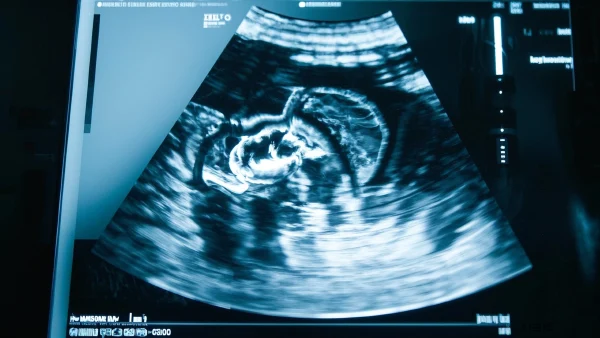

02 超声波诊断:胆囊炎的万能放大镜 🩺

- 1. 安全便捷: 超声检查没有辐射,可以反复做。像是用一把看不见的“探照灯”温柔地扫过肚皮,实时显示胆囊的大小和形态。

- 3. 发现异常: 超声不仅看“形”,还能通过观察胆囊壁、内腔及周围组织的细节,及时捕捉炎症的“蛛丝马迹”。

📌 医学解读: 超声技术属于一线检查工具(Hanna, S. F. et al., 2019),接受检查时无需特殊准备,体验几乎没有不适。